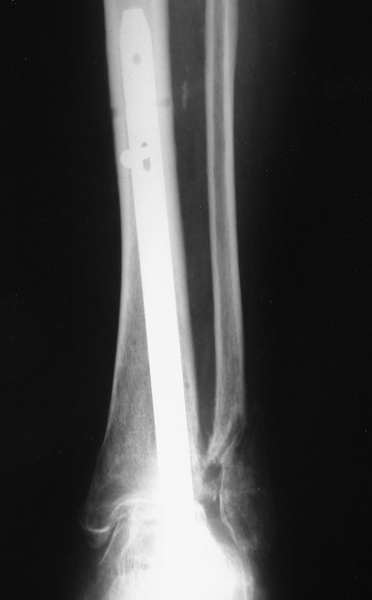

Можно: 65-летняя пациентка, оперирована по поводу несросшегося в гипсе перелома лодыжек с патологической вальгусной установкой стопы и выраженным нарушением опрной функции. Оперирована через 6 месяцев после травмы. Рентгенограммы через 4 месяца после операции.

Существуют специальные системы для артродеза голеностопного сустава. См. приложение

Уважаемый А.Семенистый. Складывается впечатление, что вы выполнили трехсуставный артродез, уж больно длинные блокирующие винты. Не мешают ли они пациентке при ходьбе?

Да конечно винты длинноваты! Мешают ли ходить? Во всяком случае субьективно пациентка удовлетворена. Ходит, естевственно, хуже чеи до травмы, но намного лучше, чем до операции.